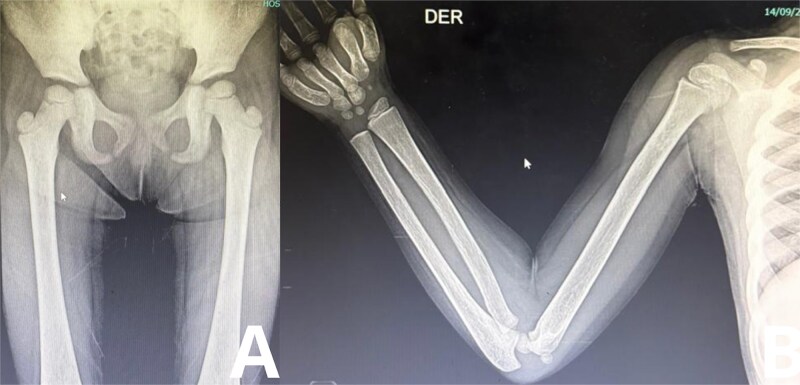

朗格汉斯细胞组织细胞增生症(LCH)是一种罕见的疾病,朗格汉斯细胞浸润到各种器官,导致组织损伤。本病例描述一名确诊为LCH的6岁男性,其表现为疲劳、过度口渴、多尿和不明原因的体重增加等症状恶化。x线检查显示颅骨和长骨有广泛的溶骨性病变,符合LCH。此外,通过激素检测和影像学证实,患者出现明显的内分泌功能障碍,包括甲状腺功能减退、尿崩症和肾上腺功能不全。该病例强调了在LCH患者中考虑内分泌功能障碍的重要性,并强调了多学科方法在管理复杂病例中的作用。激素替代治疗,以及LCH的化疗开始,患者表现出临床改善。

Langerhans cell histiocytosis (LCH) is a rare disorder in which Langerhans cells infiltrate various organs, causing damage to tissues. This case describes a 6-year-old male diagnosed with LCH, who presented with worsening symptoms of fatigue, excessive thirst, polyuria, and unexplained weight gain. Radiographic findings revealed extensive osteolytic lesions in the skull and long bones, consistent with LCH. Additionally, the patient developed significant endocrine dysfunction, including hypothyroidism, diabetes insipidus, and adrenal insufficiency, as confirmed through hormonal assays and imaging. The case emphasizes the importance of considering endocrine dysfunction in patients with LCH and underscores the role of a multidisciplinary approach in managing complex cases. Hormonal replacement therapy, along with chemotherapy for LCH, was initiated, and the patient showed clinical improvement.